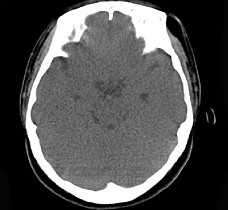

女,31岁,在左眶外上缘发现一包块,质软,余所见无明显异常。如图所示病灶应诊断为 ( ) 2YJB-16841.jpg 2YJB-16842.jpg 2YJB-16843.jpg 2YJB-16844.jpg

题型: 单选题 分类: 眼科学

• A.畸胎瘤

• B.错构瘤

• C.脂肪瘤

• D.表皮样囊肿

• E.淋巴管瘤